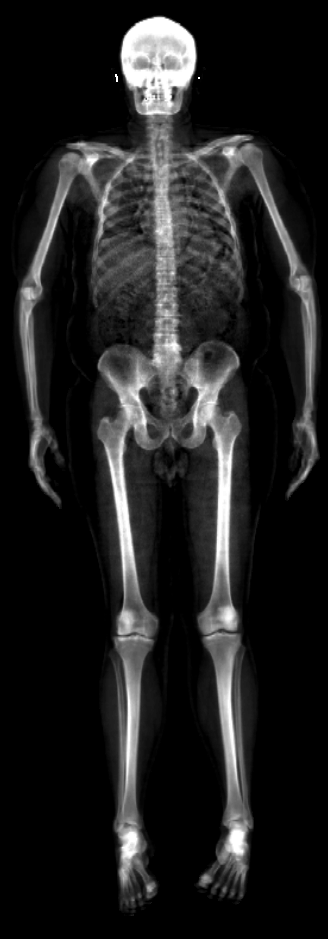

Table 1 presents the results on the test set. In the first row we evaluate the skeletons from Sec. 3.5 to validate that they faithfully match the masks . We obtain mean intersection percentages of and and mean HDs of and pixels for male and females, respectively. OSSO obtains mean intersection percentages of and and mean HDs of and pixels, while AT obtains mean intersection percentages of and and mean HDs of and pixels for male and females respectively. Consistently, the OSSO predictions have higher mean intersection values and lower HD than those of AT.

The presented metric has a limitation: predicting all the skin volume as bone would obtain a perfect result (, ). In Fig. 4 and Sup. Mat. we show that visually, OSSO’s predictions are coherent and match the DXA bone images better than Anatomy Transfer. In Sup. Mat. we provide examples of subjects with high Body Mass Index, for which Anatomy Transfer predicts a stretched skeleton, while ours are closer to the DXA skeleton mask.

In Figure 19, we present a qualitative comparison between our OSSO predictions and the ones from Anatomy Transfer. This results complement Sec. 5.3 of the main document.

From the DXA test set, we select 5 subjects spanning the dataset BMI distribution. From the skin alignment , we infer the skeleton and compare it to the subject’s skeleton DXA image. We denote the skeleton inferred with AT and the skeleton inferred with OSSO. is the mask rendered from the mesh .

As can be seen from the images, our predictions do better capture the global shape of the skeletons. Particularly, Anatomy Transfer often estimates the location of the hips to be too low with respect to the actual hips location. Our method predicts a skeleton which is visually closer to the one observed in the DXA images.